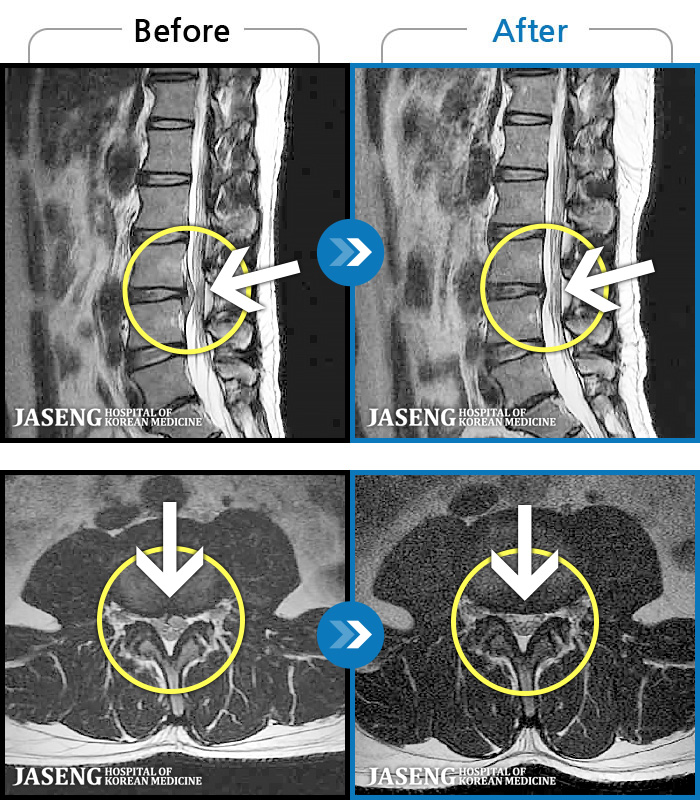

푸쉬업을 여러 번 반복한 뒤 극심한 하요부 통증 및 우측 하지부 저림

2024.03.21 ~ 2024.09.23